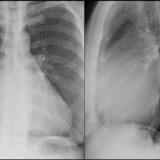

Cardiomegaly, esp RA PA

Date: 01/26/2009

Views: 2921

Cardiomegaly, esp RA Lat

Views: 3037